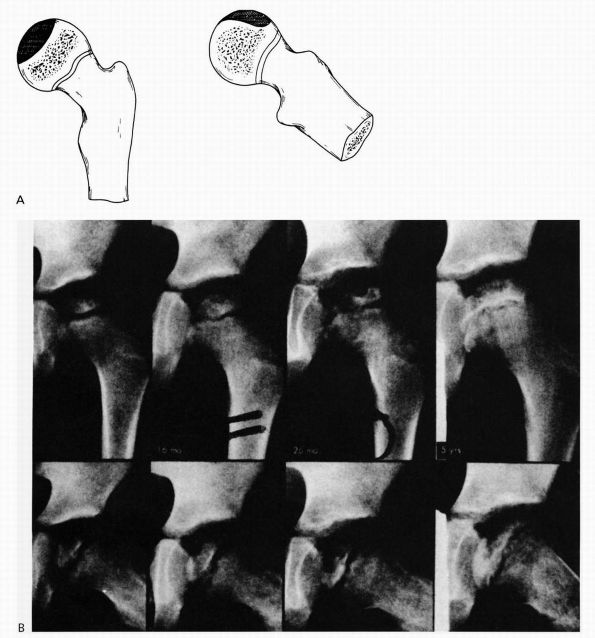

promote ossification of the defect and to correct the varus deformity,

allowing restoration of the mechanical advantage of the hip abductors

to improve gait and to equalize limb lengths. In progressive coxa vara,

the natural history suggests increasing deformity (Figure 15-28),

decreasing function, and early degenerative joint disease. The general

indications for surgical treatment include increasing coxa vara and a

neck-shaft angle of less than 100°. In mild, nonprogressive cases with

a neck-shaft angle of greater than 100° and a Hilgenreiner epiphyseal

angle of less than 45°, resolution of the defect may occur, and

observation of the patient with serial follow-up radiographs is

indicated. In patients with a limp, progressive deformity, and a

Hilgenreiner epiphyseal angle of greater than 60°, intertrochanteric or

subtrochanteric abduction osteotomy is the treatment of choice (Figure 15-29).

In these patients, the neck-shaft angle should be restored to decrease

the shear stress across the vertical defect. With surgery, the defect

generally heals, but growth plate arrest may be seen in a significant

number of patients, leading to limb length inequality. Generally,

patients older than 5 years of age at the time of surgery maintain

their correction.

![]() |

|

FIGURE 15-28. Coxa vara development. Note triangular fragment and worsening of condition over a 2-year period (bottom).